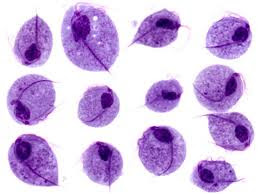

Trichomonas vaginalis

Important features- it is a pear-shaped organism with a central nucleus and four anterior flagella; and undulating membrane extends about two-thirds of its length. It exists only as a trophozoite form, and measured 7-23μm long & 5-15μm wide. Transmission is by sexual intercourse.